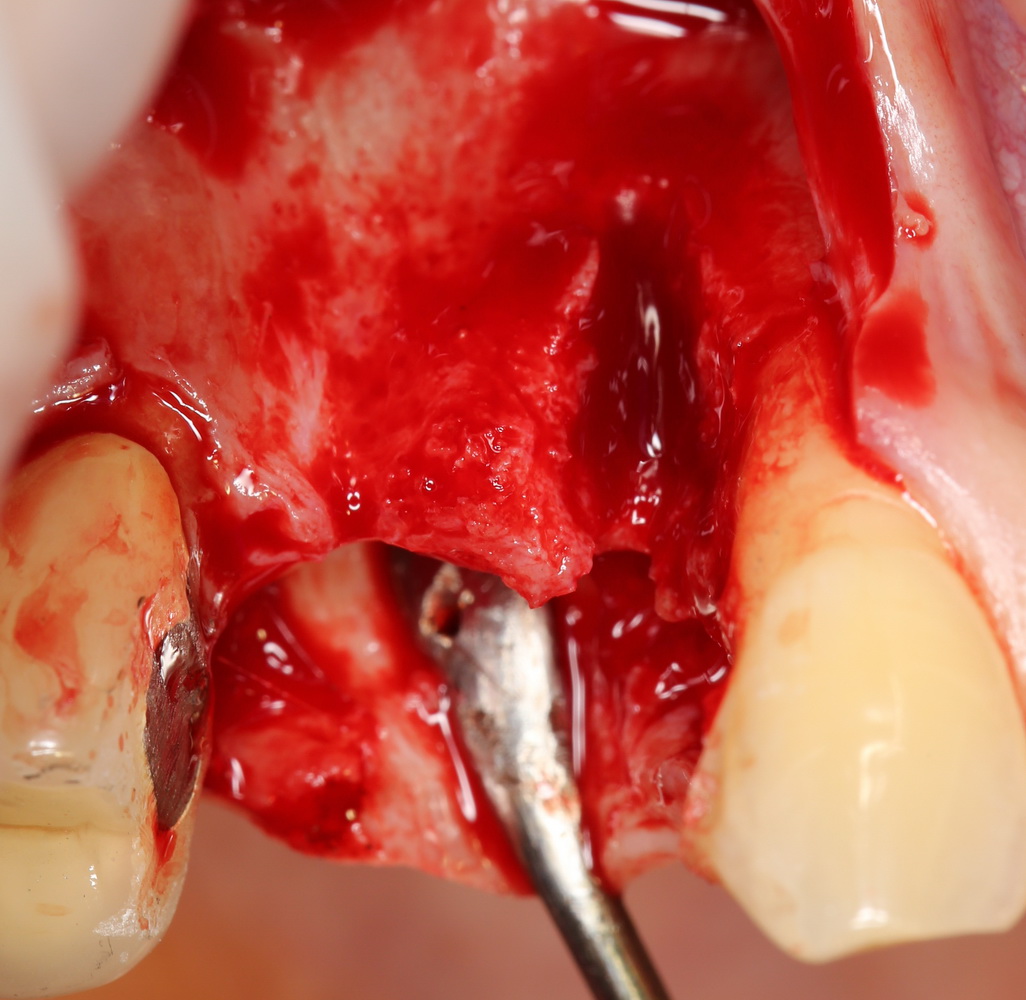

И вроде бы, все неплохо, но когда мы скелетируем костную ткань, то видим следующее:

Можно ли поставить импланты? Теоретически, если использовать импланты диаметром 3,0 мм — вполне возможно. Но как это будет потом выглядеть? Большие коронки на тоненьких имплантах с тонкой десной? А если эти зубы еще попадают в эстетически значимую зону и видны при улыбке? А если это еще и девушка, которая собирается замуж? И вот тут встает вопрос о размерах и позиционировании имплантов, который тянет за собой вопрос об остеопластике.